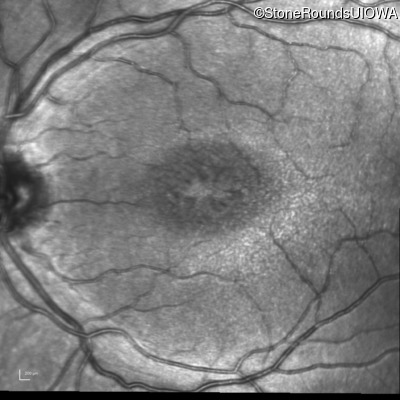

Infrared Fundus Photograph - Right - 20/63 -2

Exemplar

Infrared Fundus Photograph - Left - 20/50 -2